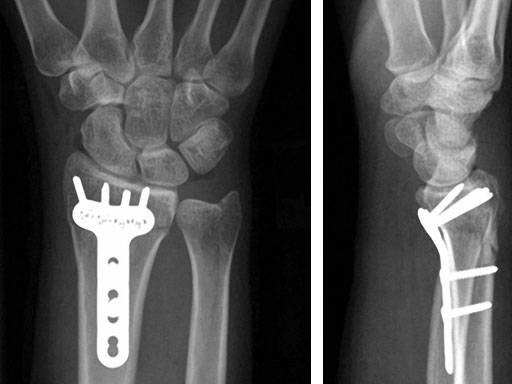

Case 3: Multifragmentary distal radius fracture with extension into the diaphysis

A 26-year-old man suffered a multifragmentary fracture of his left distal radius with extension into the diaphysis (AO23 C3.3) (Fig 1). The VA LCP Extra Long Two-Column plate was used for fixation (Fig 2). After initial immobilization, the plate provided a good postoperative fixation of the fracture.

The fracture showed primary bone healing without callus formation. At the 3-month follow-up, the patient was full weight bearing with excellent clinical function (Fig 3). The radiological follow-up can be technically challenging due to the correct focus of the central ray.